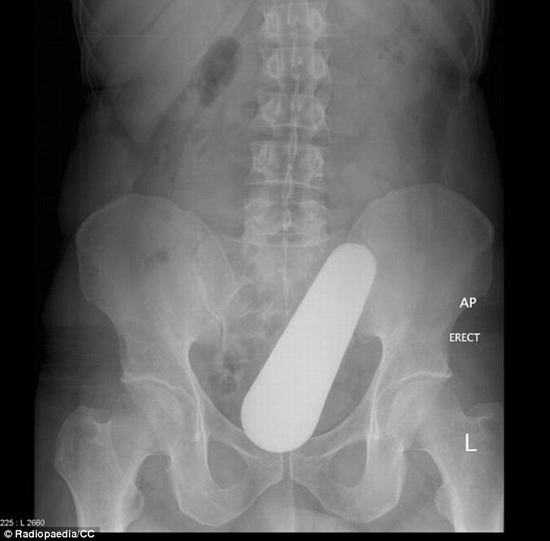

Trường hợp khác, sex-toy được đưa vào quá sâu bên trong âm đạo một phụ nữ.